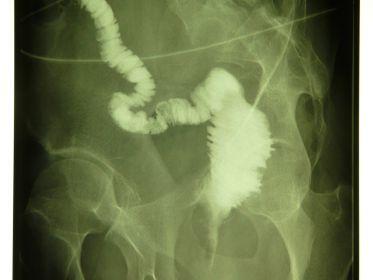

Crohn’s disease, an inflammatory bowel disease (IBD), is characterized by full thickness wall lesions of the small and/or large intestine, along with anal lesions. First line of treatment is medical (steroids and/or immuno-suppressive drugs). In cases of failure or complications, laparoscopic surgical resection is advised.

In Western countries, most of the people over 60 years of age, have sigmoid or colonic diverticula at colonoscopy. In cases of acute inflammation (sigmoid diverticulitis), antibiotic therapy is mandatory. After two or more acute episodes, elective sigmoid resection is advised using laparoscopic robotic technology.